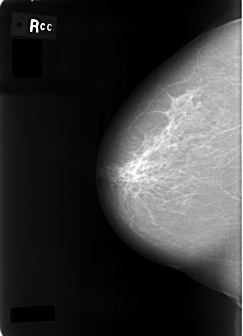

C_0002_1.RIGHT_CC

RIGHT_CC LINES 5704 PIXELS_PER_LINE 4120 BITS_PER_PIXEL 12 RESOLUTION 50 NON_OVERLAY